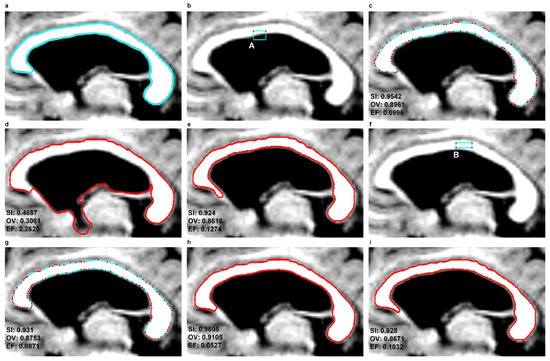

In this study, the same location of the seed contour was adopted for three models—EM, DRLSE and SBGFRLS—along the CC cross-section determined in each instance for specific sets of brain MR images coming from various patients. The seed contour was placed inside the CC cross-section as in the example from Figure 7f.

Figure 7c–e,g–i illustrate example segmentation results produced by EM, DRLSE and SBGFRLS for two different methods of initialisation presented in Figure 7b,f. Similar segmentation results were produced by the EM and SBGFRLS models, as presented in Figure 7c,e,g,i. In the case of the DRLSE model, the location of the seed contour has a major impact on CC segmentation results. Example differences are visible for the following pairs:

-

Figure 7b,d. When the seed contour is only partly located inside the CC cross-section being approximated, as illustrated by the example from Figure 7b, the CC segmentation produced is wrong. Figure 7d clearly shows an extracted, very large extra fraction (EF = 2.2625).

Figure 7f,h. If the seed contour has been placed inside the CC cross-section as in Figure 7f, a very accurate CC segmentation can be produced, like in the example from Figure 7h.

Figure 7. An example illustrating the results of corpus callosum segmentation using the EM, DRLSE and SBGFRLS methods for two different contour initialisations—A and B–based on an MR image in the sagittal plane from the ’miriad_188_AD_M_01_MR_1’ set (a) a contour traced by a physician ( E 1 ); (b) a rectangular seed contour: A; (ce) final contours produced by the EM, DRLSE and SBGFRLS methods with initialisation A; (f) a rectangular seed contour: B; (gi) final contours produced by the EM, DRLSE and SBGFRLS methods with initialisation B.